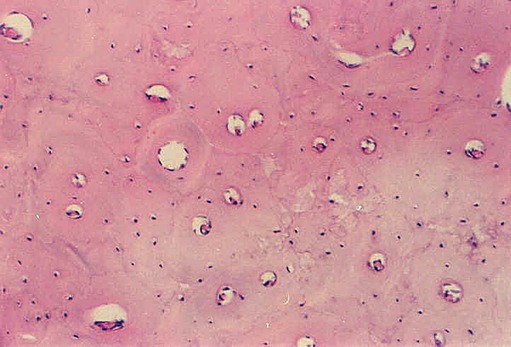

The Haversian systems are not as well delineated in compact bone from rib, shown in the photographs below, but the circular pattern can be visualized. Find osteocytes, Haversian canals and Volkman's canals.